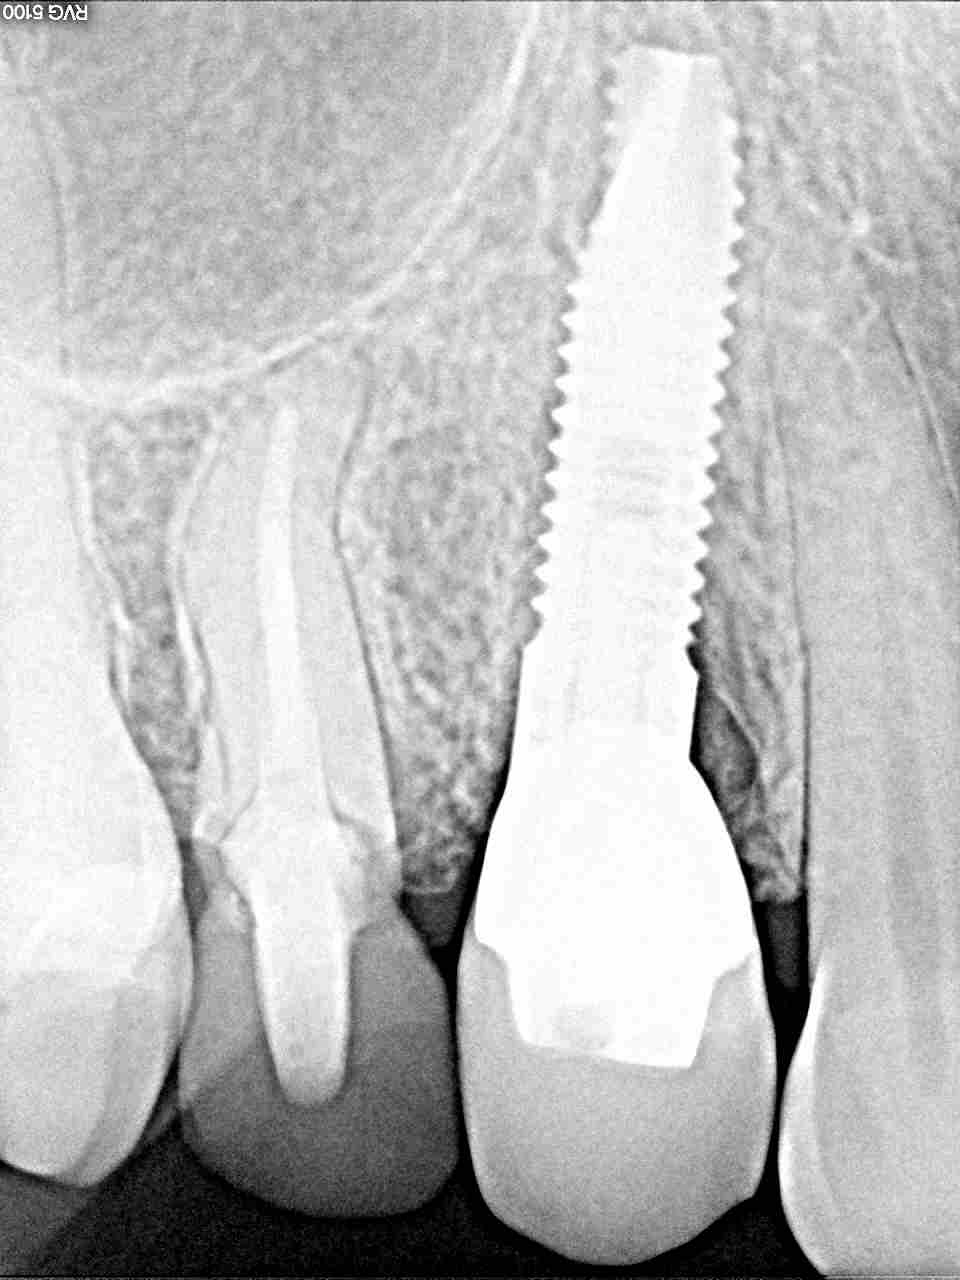

右上の4番になります

こちらもカスタムにて作成しています

印象時になります

最終補綴時になります

4mmの13mmというインプラントを埋入しています